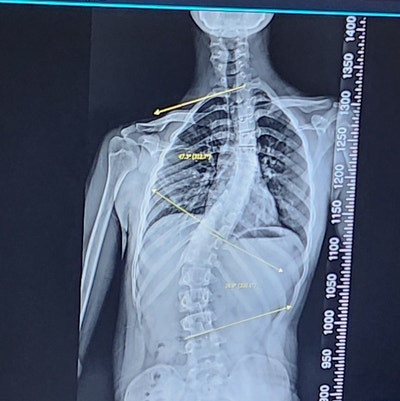

[트레이닝 기록] 자폐성 장애 학생의 측만 교정운동

척추측만 체형교정을위해 무브멘토에서 재활운동을 진행중이신 회원님 측만 교정 운동은 커브타입이나 콥스...